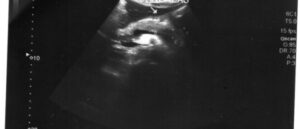

Такое заболевание, как гемангиома селезенки, встречается крайне редко. Это доброкачественная опухоль, находящаяся на поверхности органа. Врач на УЗИ, исследуя внутренние органы по абсолютно другому поводу, может в придачу выяснить, что у человека есть гемангиома. Сама по себе она может мало беспокоить обладателя и на протяжении длительного времени не проявляться симптомами. Причины паниковать при таком диагнозе …